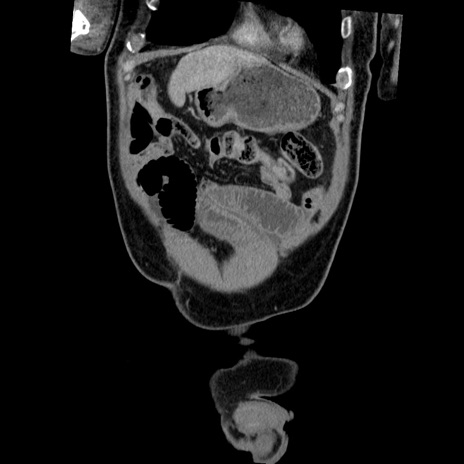

横断像